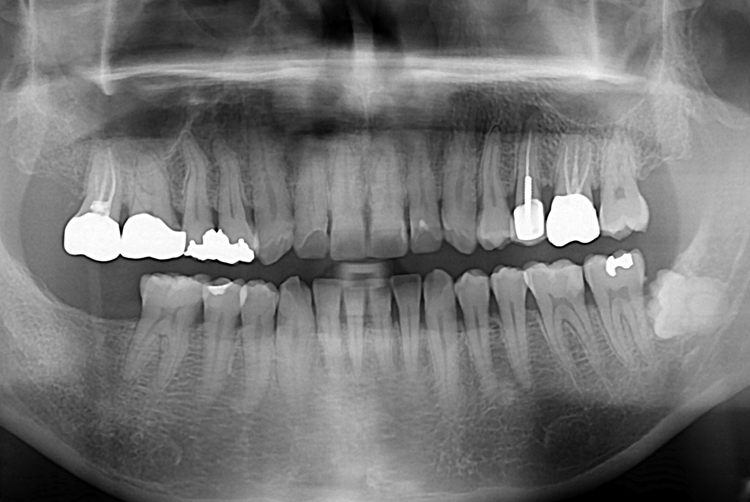

[임플란트] 어금니 임플란트

치료전 : 2016-07-26